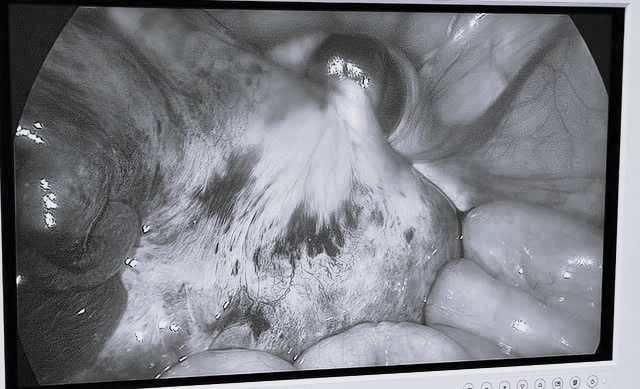

| Hình ảnh khối u buồng trứng xoắn của bệnh nhi. Ảnh BVCC |

Bệnh nhi được phẫu thuật nội soi. Khi tiến hành phẫu thuật, bác sĩ quan sát thấy buồng trứng trái to khoảng 50x60 mm bị xoắn 2 vòng, hoại tử tím đen nên đã tiến hành cắt trọn buồng trứng trái.